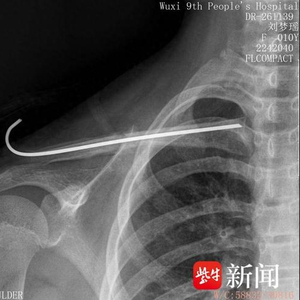

术后一个月骨愈合摄片

据悉,常规手术需行切开复位钢板内固定,但大切口一方面易影响骨折断端血供,另一方面易造成切口疤痕从而影响美观。近年来,随着微创治疗理念的推广,无锡九院小儿骨科已常规开展小切口辅助复位行克氏针、髓内钉固定手术。但孩子不同于成人,大多锁骨髓腔细小、闭合复位困难,因此这一微创手术操作对精准度提出了更高要求。印飞医生和团队通过“天玑”骨科机器人详细采集患儿小紫的数据,精准规划手术路径,锚定进针位置和方向后,“按图索骥”完成锁骨干骨折的闭合复位克氏针髓内固定手术。术后,小紫的伤处仅留下数枚针眼孔。

小儿骨科副主任林伟枫介绍,骨折患儿是临床中的一类特殊群体,手术治疗的目的是减轻疼痛、降低后遗症并尽早帮助他们重返校园。在“天玑”骨科机器人的辅助下,可真正实现“零切开”锁骨骨折治疗,既避免了二次手术风险,又不会留有明显手术疤痕。